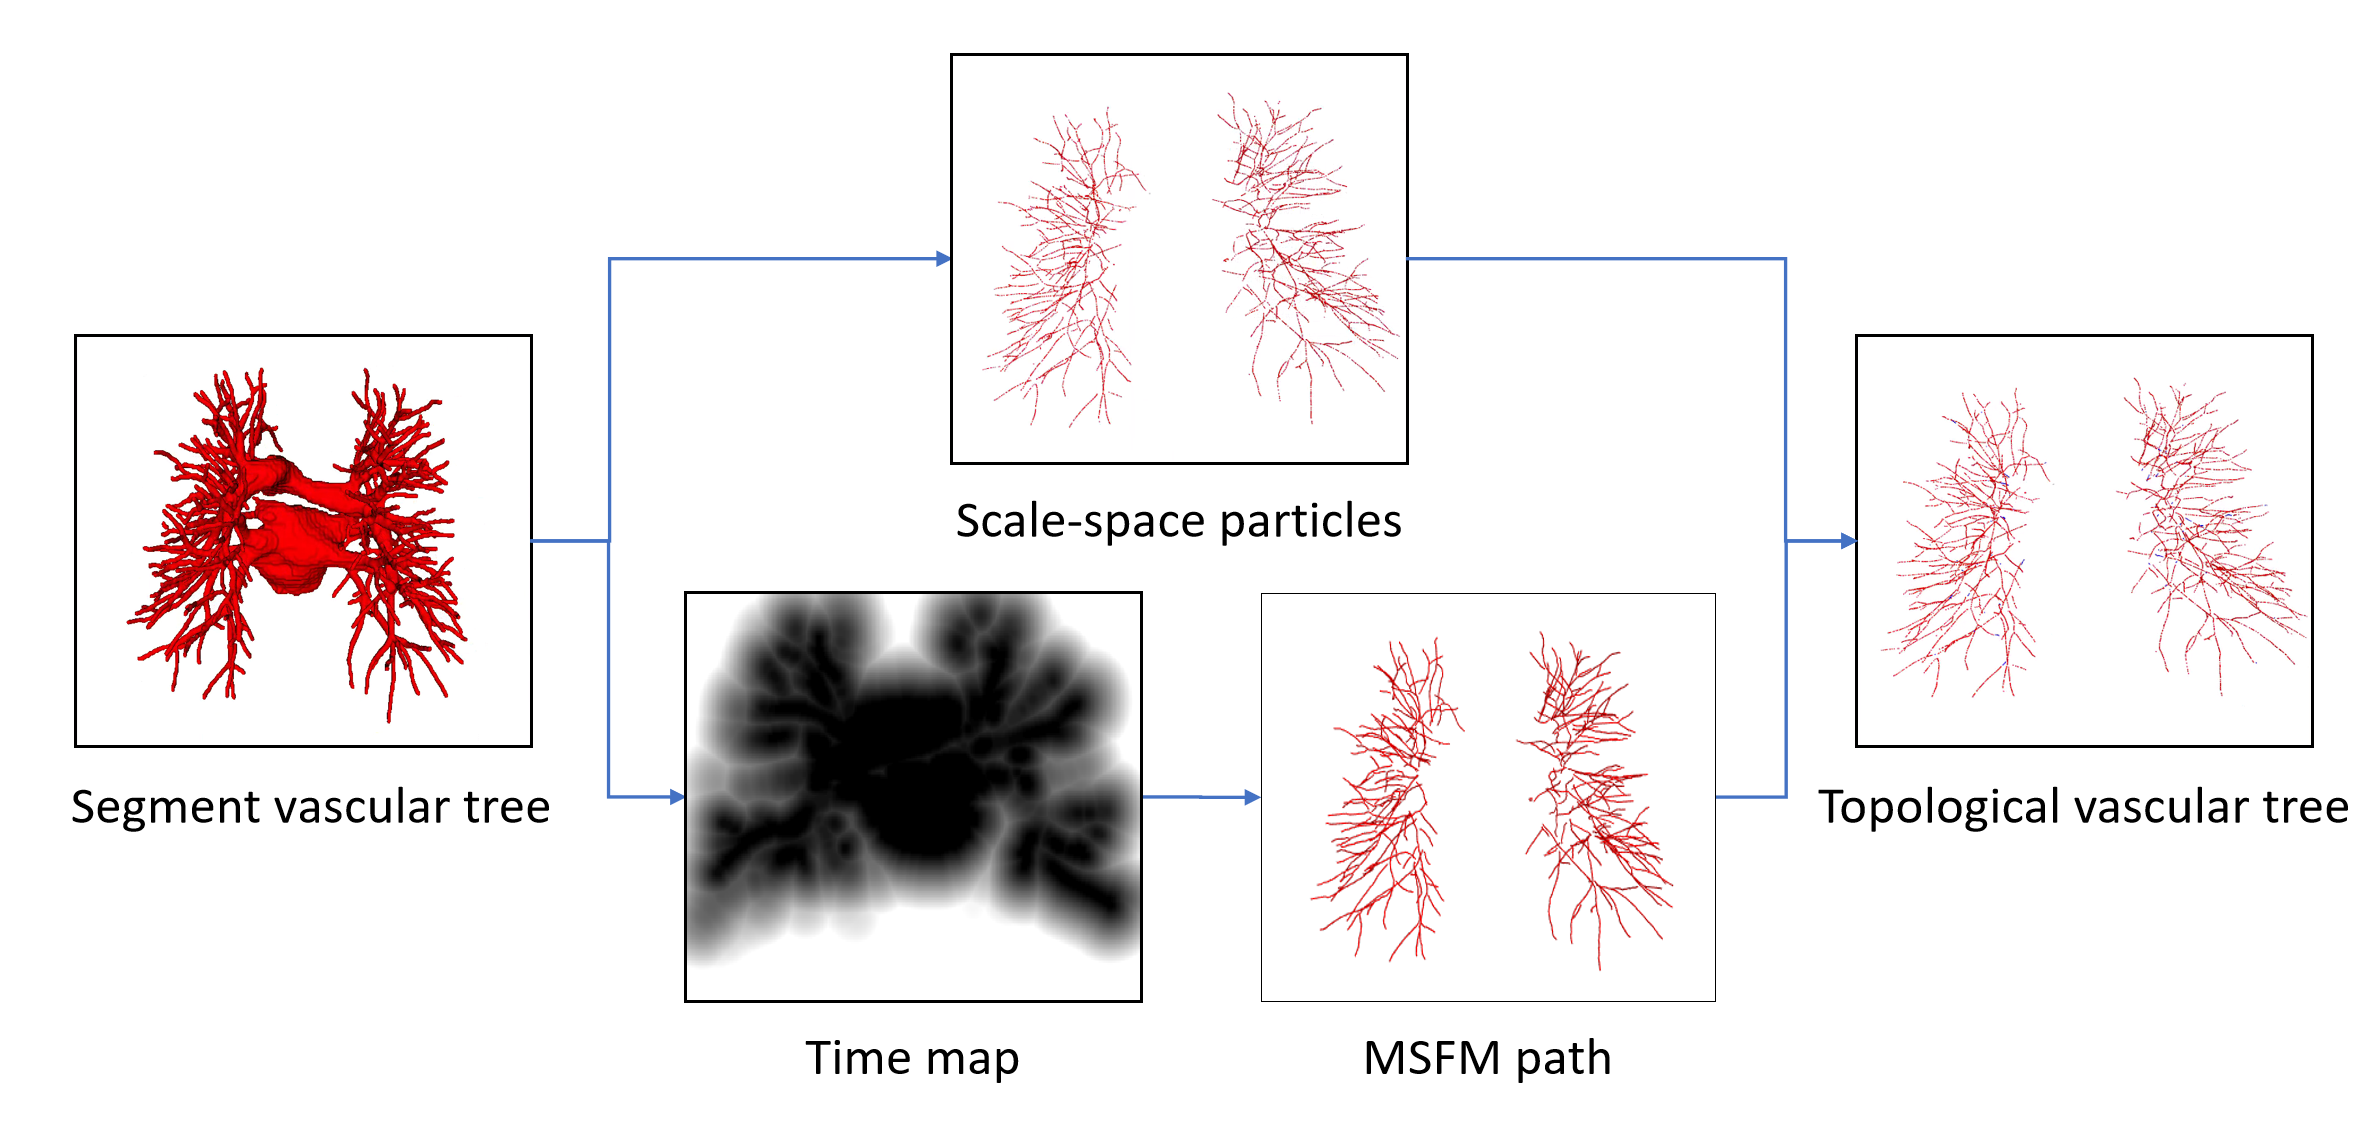

The overall framework of pulmonary A/V separation method in this paper is shown in Fig. 3, including vascular tree topology extraction, preliminary classification of Twin-Pipe network and topology optimizer refined classification pulmonary A/V results.

In the vascular tree topology extraction module, the vessels and the vessels near the hilum of the lung are segmented from thoracic CT images respectively, and a full vascular tree can be obtained by fusing them together. Then the topology is extracted, and the distance transform is used to guide and compensate the missing points flexibly. The vascular tree is represented as a collection of particles, and the vessel particles are transformed into topological trees. In Twin-Pipe network, 3D patches are taken from each particle on the topological tree as the center, and the whole vessel segment and the terminal branch vessel are trained separately from the topological tree, and the preliminary classification results of vessel particles are obtained. Finally, in optimizer and A/V result module, topological subtrees and topological branches are extracted from the topological tree, and the branch confidence is calculated to prune the subtree. Optimization of A/V classification using topological connectivity. Then, the pulmonary A/V topology is reconstructed and the A/V near the hilum are fused to obtain the pulmonary A/V results.

The proposed method begin with vascular tree segmentation. Vascular trees are extracted from chest CT scan by fusion of vessels[15] and vessels near the hilum of the lung. The specific process is shown in Fig. 4. And then, topology tree is constructed by skeleton topology extraction.

Due to the applicability of the skeleton algorithm and the characteristics of the vascular tree itself, it is often impossible to obtain accurate results of skeleton structure[16]. we flexibly combine the Multi-Stencils Fast Marching[17] and a scale-space particles reconstruction algorithm[18] to develop a new topomorphologic algorithm to construct the topological vascular tree.

Firstly, based on the characteristics of vascular tubular structure, the scale-space particle reconstruction algorithm was used to extract the initial skeleton of the vessel and obtain the local information of the vessel mask. Scale-space particles sampling method exploits the theory of linear scale-space to localize the features of the image described by the Hessian. The vascular tree is represented as a set of particles that each contains vessel scale, orientation, and intensity information. Therefore, particles are represented as X = {}, where represents a particle point. However, after vascular tree reconstruction, the vessels are discontinuous, which is due to the inability of this method to identify non-tubular structures, such as the junction of vessels, resulting in partial point loss. At the same time, there was no parent-child relationship between the particles.

Secondly, the skeleton extraction algorithm based on distance transform can maintain the connectivity of the vascular tree. MSFM is used to obtain the global information from the vessel mask, and the vessel point path is obtained by iteratively tracing from the end of the potential tree to the root node, where the branch online confidence score is calculated in the time map to determine whether the trace iteration should be updated or excluded from the skeleton tree. In this paper, 3D vessel mask is taken as the input with 3D coordinates x, aiming to output the vessel skeleton tree G, and a 3D spatial coordinate and radius are specified for each vessel skeleton tree G node. The degree of each vascular tree node can be between 1 and 3. However, the radius of each node of the obtained vessel tree is only an approximation and does not really reflect the vascular tubular shape, and the results after reconstruction are different from the real vascular tree to some extent.

Finally, in order to ensure the continuity and authenticity of the topology reconstruction, we flexibly combined the global and local information of the vascular skeleton. In this paper, a particle-based 26-neighborhood search method is used to extract the topological structure of the final vessels by guiding the time map to make up for the missing vessel particles. In this paper, vessel particles can be classified into three categories: terminal points (or false-positive terminal points), branching points, and bifurcating points. We indicate the number of points in the 26 neighborhoods of vessel particles as (). When the particle is the terminal point, () = 1; when the particle is the branching points, () = 2; when the particle point is the bifurcating points, () >2. Due to the presence of branch point loss or branch fracture resulting in false positive terminal points, further discrimination is needed. Travel in the direction of the terminal vessel points, and if the terminal point is still on the vessel mask after traveling, it is considered as a false positive terminal point, where the travel distance is between one and two scales. Otherwise, it is considered to be the true terminal point. For the false positive terminal points, the trajectory of the lost vessel points is obtained by MSFM in the time map, in which the time map is calculated from the 3D distance map. Finally, the complete topology tree is obtained. The process of the vascular tree topology extraction method is shown in Fig. 5 and Fig. 6. And compared with the scale-space particle reconstruction algorithm, the advantages of the vascular tree topology extraction in this paper are shown in Fig. 7.

First, we use the vascular tree topology method to extract vascular topology for the training of classification network. The current topology extraction algorithms have their own applicability, and we propose a vascular tree topology method, which fully uses their advantages to solve the problem of topological fracture caused by particle loss. As shown in Figs. 7 and 13, a complete vascular skeleton structure not only affects the vascular classification evaluation system, but also plays a crucial role in arterial/vein vessel reconstruction.